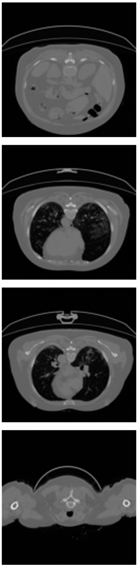

Furthermore, the CLAHE (Contrast Limited Adaptive Histogram Equalization) method is applied to overcome the contrast problems (noise and intensity inhomogeneity). CLAHE was used to intensify the contrast of the obtained images [47]. This method is a variant of AHE (Adaptive Histogram Equalization). CLAHE’s main objective is to determine the mapping for each pixel based on its neighborhood grayscale distribution using a transformation function that reduces contrast amplification in densely packed areas. In [48,49], CLAHE has shown its effectiveness in allocating displayed intensity levels in chest CT-scans. In Table 4, a comparison of the CT-scan slices before CLAHE was applied and after CLAHE was applied is shown.

Table 4.

Comparison before and after applying CLAHE preprocessing to CT-scan.